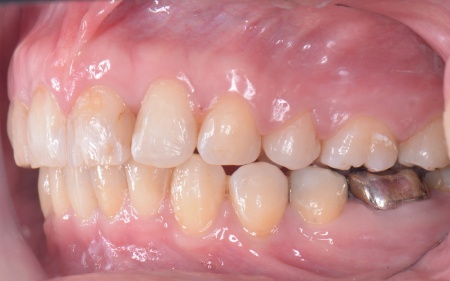

| カウンセリング | 拝見したところ、上前歯が大きく前に出ている上顎前突であり、上下の前歯が噛み合わずに口を閉じても前歯同士が接触しない「開咬(かいこう)」の状態でした。 レントゲン撮影をして詳しく調べた結果、歯の位置だけでなく、骨格的な問題があることが分かりました。 また、前歯で食べ物をうまく噛み切ることができないため、奥歯にも強い負担がかかっているだけでなく、このまま放置すると、奥歯がすり減ったり痛みが生じたりするリスクもあります。 以上のことから、噛み合わせを改善する治療が必要だと診断しました。 |

患者様の場合、骨格的な上顎前突が噛み合わせを乱している主な原因であることから、矯正治療では前歯を後方へ大きく動かすためのスペースを確保する必要があります。 そのため、今回は以下2つの方法を提案しました。 ①抜歯後、アンカースクリューを用いたワイヤー矯正 メリット:骨格的な上顎前突に対応しやすく、前歯を大きく後方へ動かすことができる ②取り外し可能な装置を使用するマウスピース矯正 メリット:装置が透明で目立ちにくく、取り外しができる 以上のメリットとデメリットを丁寧にお伝えしたところ、患者様は①のアンカースクリューを用いたワイヤー矯正を選択されました。 まず、上顎の左右奥歯を抜き、前歯を後方に動かすためのスペースを確保します。 治療の結果、前歯が正しく噛み合うようになり、横顔のバランスも整いました。 矯正治療終了後は、歯が元の場所に戻らないよう上下前歯に保定装置(リテーナー)を装着し、治療を終了しています。 |